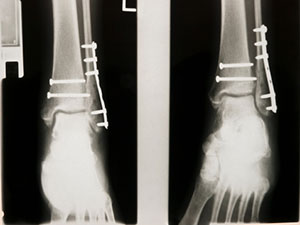

Оперативное лечение всем пациентам с ВПДКК проведено в период с 1-х по 7-е сутки с момента получения травмы, в среднем через 3,8±1,6 суток. Использовали все актуальные современные методы остеосинтеза, включая интрамедуллярный, накостный, внеочаговый компрессионно-дистракционный, в том числе технику малоинвазивного остеосинтеза с применением накостной пластины — MIPO (minimally invasive plate osteosynthesis).